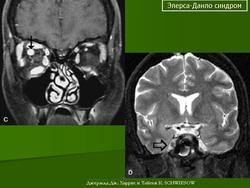

4. Кифосколиотический тип.

Наследуется по аутосомно-рецессивному типу. Основные диагностические критерии: генерализованная гипермобильность суставов, выраженная мышечная гипотония при рождении, прогрессирующий (с рождения) сколиоз, кифоз, хрупкость склер разрывы глазного яблока. Дополнительные диагностические критерии: хрупкость тканей, иногда атрофичные рубцы, склонность к кровоизлияниям, разрывы артерий, марфоноидный фенотип, микрокорнеа, рентгенологически выявляемая выраженная остеопения, положительный семейный анамнез ( в том числе больные сибсы).

Следует отметить, что наличие трех основных критериев является основанием для предположения диагноза и требует лабораторного обследования. Причем мышечная гипотония может быть очень выраженной и обусловливает задержку моторного развития. Выраженный сколиоз приводит к тому, что во второй-третьей декаде жизни больные теряют способность передвигаться самостоятельно. Хрупкость тканей глаза является причиной разрыва глазного яблока при малейшей травме. Согласно последним данным, тяжелые глазные осложнения встречаются гораздо реже, чем предполагалось ранее. При этом типе СЭД дефект в синтезе коллагена заключается в изменении фермента лизил-гидроксилазы, которая катализирует гидроксилирование боковых лизиновых цепей, необходимых для перекрестных связей между соседними коллагеновыми молекулами при формировании тройной спирали.